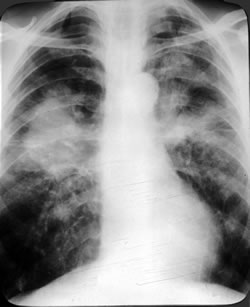

Neumonía: Enfermedad principalmente de origen infeccioso que afecta a las unidades de intercambio gaseoso del pulmon es decir, los alveolos. Puede ser desde un grado leve que amerite solamente antibioticos por vía oral y manejo en casa hasta ser muy serias al grado de amenazar la vida siendo imprescindible el tratamiento en una terapia intensiva. Los agentes causales más comunes son: streptococo pneumoniae, Mycoplasma Pneumoniae, Chlamydia Pneumoniae, Haemophylus Influenzae, entre otros. Los síntomas son fiebre, tos con expectoración, dolor torácico y dificultad respiratoria.